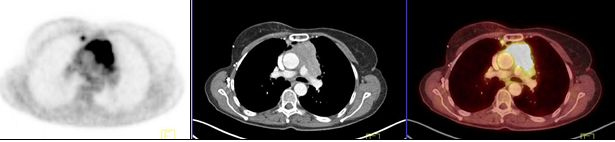

Los timomas de bajo grado (fig. 2) se caracterizaron por ser tumores bien delimitados, con estructura interna heterogénea, sin invasión a la grasa o estructuras adyacentes; presentaron hipermetabolismo leve a moderado, con un SUVmax promedio de 4,3 (rango 3,3 a 5,5) y en 2/5 hubo circulación colateral periférica.